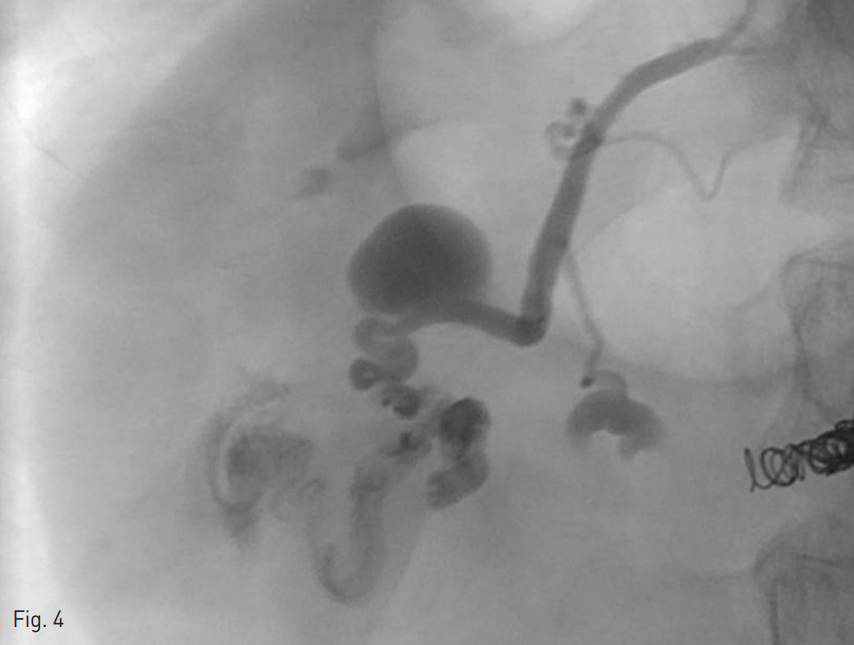

Fig. 4

After superselection for superior feeding vessel, portogram shows contrast congestion at ectopic varices.

또한 상부 영양혈관을 마이크로 카테터로 초선택하여 조영술을 시행하였고 (Fig. 4), 시행한 조영술 상 조영제의 저류가 관찰되어 glue와 Lipiodol 혼합물을 이용해 색전술을 시행하였다.